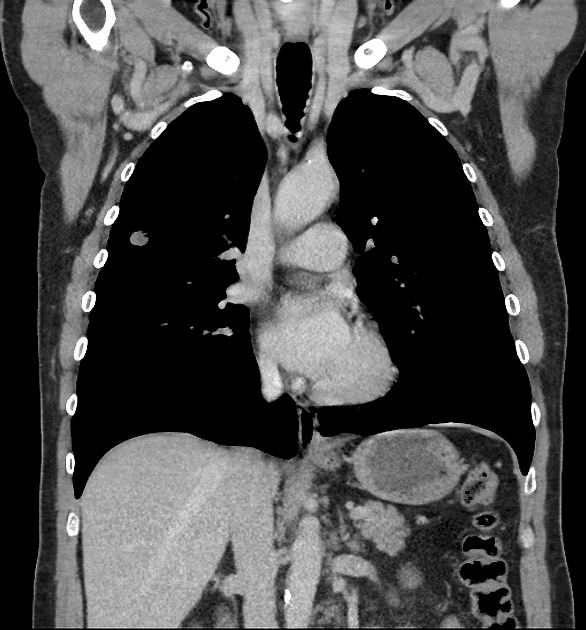

U phổi

» Thông tin: Nam giới – 70 tuổi.

» Lâm sàng: Ho / Tiền sử hút thuốc lá.

# Ung thư biểu mô tuyến (Adenocarcinoma).